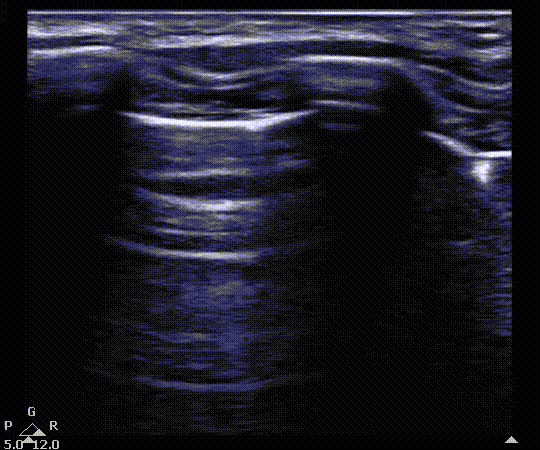

View US images that rule in or rule out a pnuemothorax